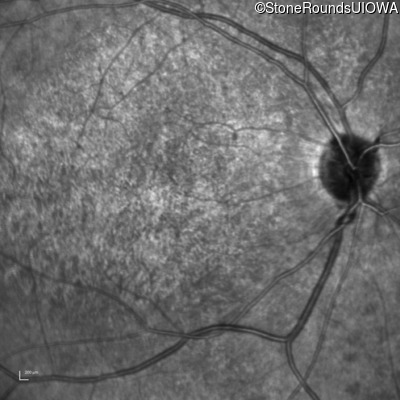

Infrared Fundus Photograph - Left - 20/200 -2 sc

Exemplar